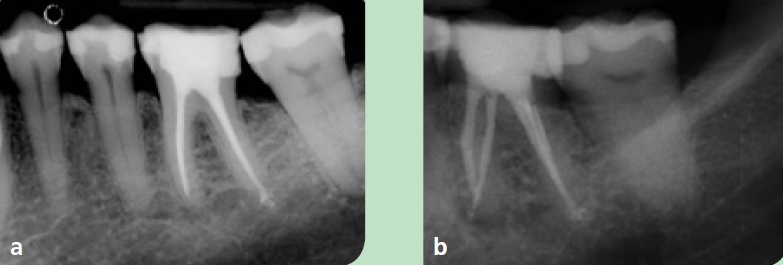

Im Anschluss an die Aufklärung über die Behandlungsoptionen wünschte die Patientin die endodontische Revisionsbehandlung. Nach intraligamentärer Anästhesie und Applikation von Kofferdam wurde unter dem OP-Mikroskop (OMS2350, Zumax Medical, Jiangsu/China) die Zugangskavität mit dem Diamantinstrument 15802* und anschließend dem EndoGuard (H269QGK*) angelegt. Die Darstellung des Pulpenkammerbodens und der Kanalorificien mit dem alten Obturationsmaterial erfolgte mit extralangen Rosenbohrern EndoTracer* (Abb. 2). Bei der intrakanalären Diagnostik konnte zudem in der distalen Wurzel ein zweites, bei der Primärbehandlung nicht aufbereitetes Kanalsystem dargestellt werden. Im koronalen Drittel wurde das alte Füllmaterial mit dem Endo ReStart-Opener (RE10L15*) entfernt, im mittleren und apikalen Drittel mit der Endo ReStart- Feile (RE05L21*), beides jeweils bei 300 Upm und einem Drehmoment von 1,8 Ncm ohne Einsatz eines Lösungsmittels. Die restliche Entfernung und das Sondieren der Kanalsysteme wurde mit Handfeilen bis zur ISO-Größe 012 (17525*) vorgenommen. Die Länge der Kanalsysteme wurde durch Handfeilen mit dem EndoPilot mobil endometrisch bestimmt (EP0013*). Es erfolgten die maschinelle Etablierung eines Gleitpfades mit dem PathGlider (PG03L25*) und die Aufbereitung der Kanalsysteme unter kontinuierlicher Spülung mit 6 % NaOCl (CanalPro NaOCl, Coltène/ Whaledent, Langenau). Die durch apikales Messen bestimmte Größe der Kanalsysteme ergab in den mesialen Kanalsystemen eine notwendige Aufbereitung bis zur ISO-Größe 035 und in den distalen Kanalsystemen bis zur ISO-Größe 045. Mechanisch aufbereitet wurde mit den F360-Feilen (F04L25*) im EndoPilot mobil bei 1,8 Ncm und 350 Upm (Abb. 3).

Jedes Kanalsystem wurde anschließend chemisch mit Canal-Pro NaOCl und jeweils 3 x 30 Sekunden mit der Spülspitze SF65 (4615*) schallaktiviert gereinigt. Die letzte aktivierte Spülsequenz wurde mit 17 % EDTA (CanalPro EDTA, Coltène/ Whaledent) durchgeführt. Danach wurden die Kanalsysteme mit den zum F360-System passenden Papierspitzen (PPF04*) getrocknet. Die Obturation der Kanalsysteme wurde in einer Hybridtechnik mittels „continuous wavetechnique“ (Downpack) und „Multi-Fill-Technik“ (Backfill) mit zum F360-System passender Guttapercha (GPF04*) und einem Sealer auf Epoxid-Polymer-Basis durchgeführt (Easy- Seal*) (Abb. 4). Die temporäre koronale Restauration des Zahnes erfolgte mit einem dualhärtenden Komposit (Dentin-Bond Evo/DentinBuild Evo opakweiß*). Die röntgenologische Kontrolle zeigte eine dichte Versiegelung des kompletten Kanalsystems (Abb. 5a u. b) und die Patientin wurde zur weiteren prothetischen Therapie an den Hauszahnarzt zurücküberwiesen.